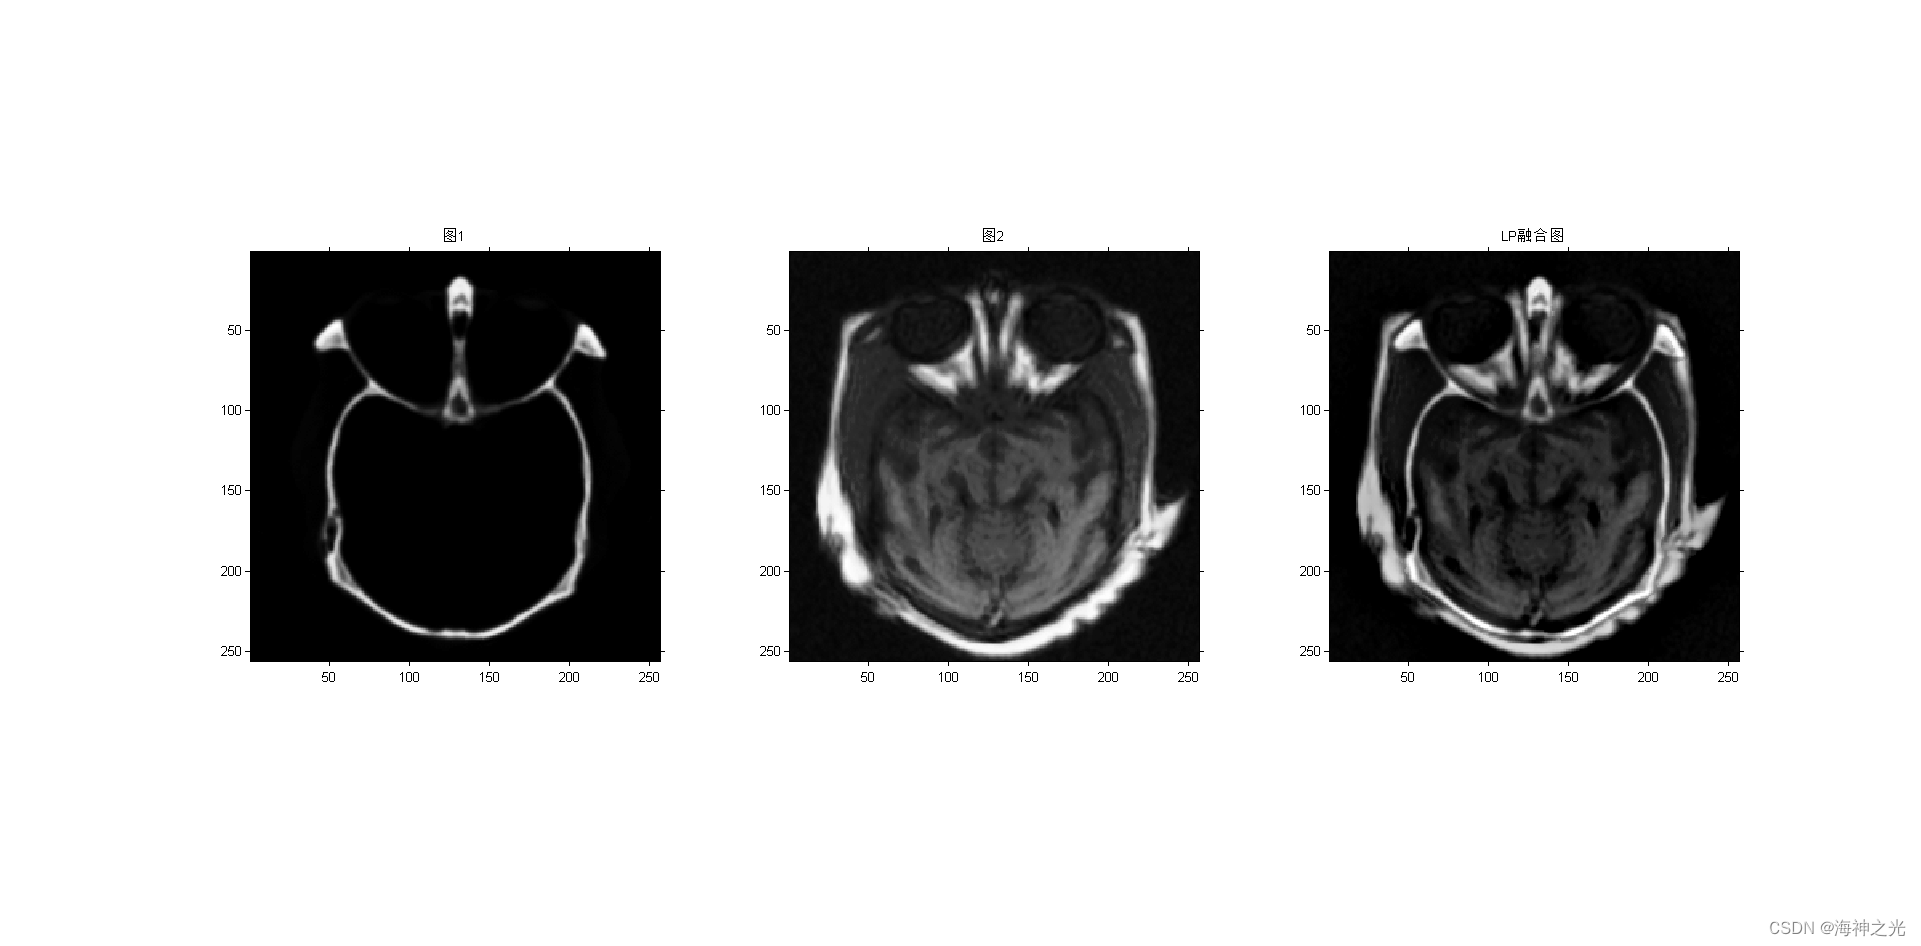

figure;subplot(131);imshow(image_input1);title(‘图1’)

subplot(132);imshow(image_input2);title(‘图2’)

subplot(133);

F = lp_fuse(A, B, level, 3, 3); %LP

title(‘LP融合图’)

⛄三、运行结果